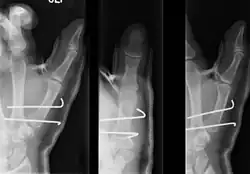

- For Bennett fractures where there is between 1 mm and 3 mm of displacement at the trapeziometacarpal joint, closed reduction and percutaneous pin fixation (CRPP) with Kirschner wires is often sufficient to ensure a satisfactory functional outcome. The wires are not employed to connect the two fracture fragments together, but rather to secure the first or second metacarpal to the trapezium.

Regardless of which approach is employed (nonsurgical, CRPP, or ORIF), immobilization in a cast or thumb spica splint is required for four to six weeks.